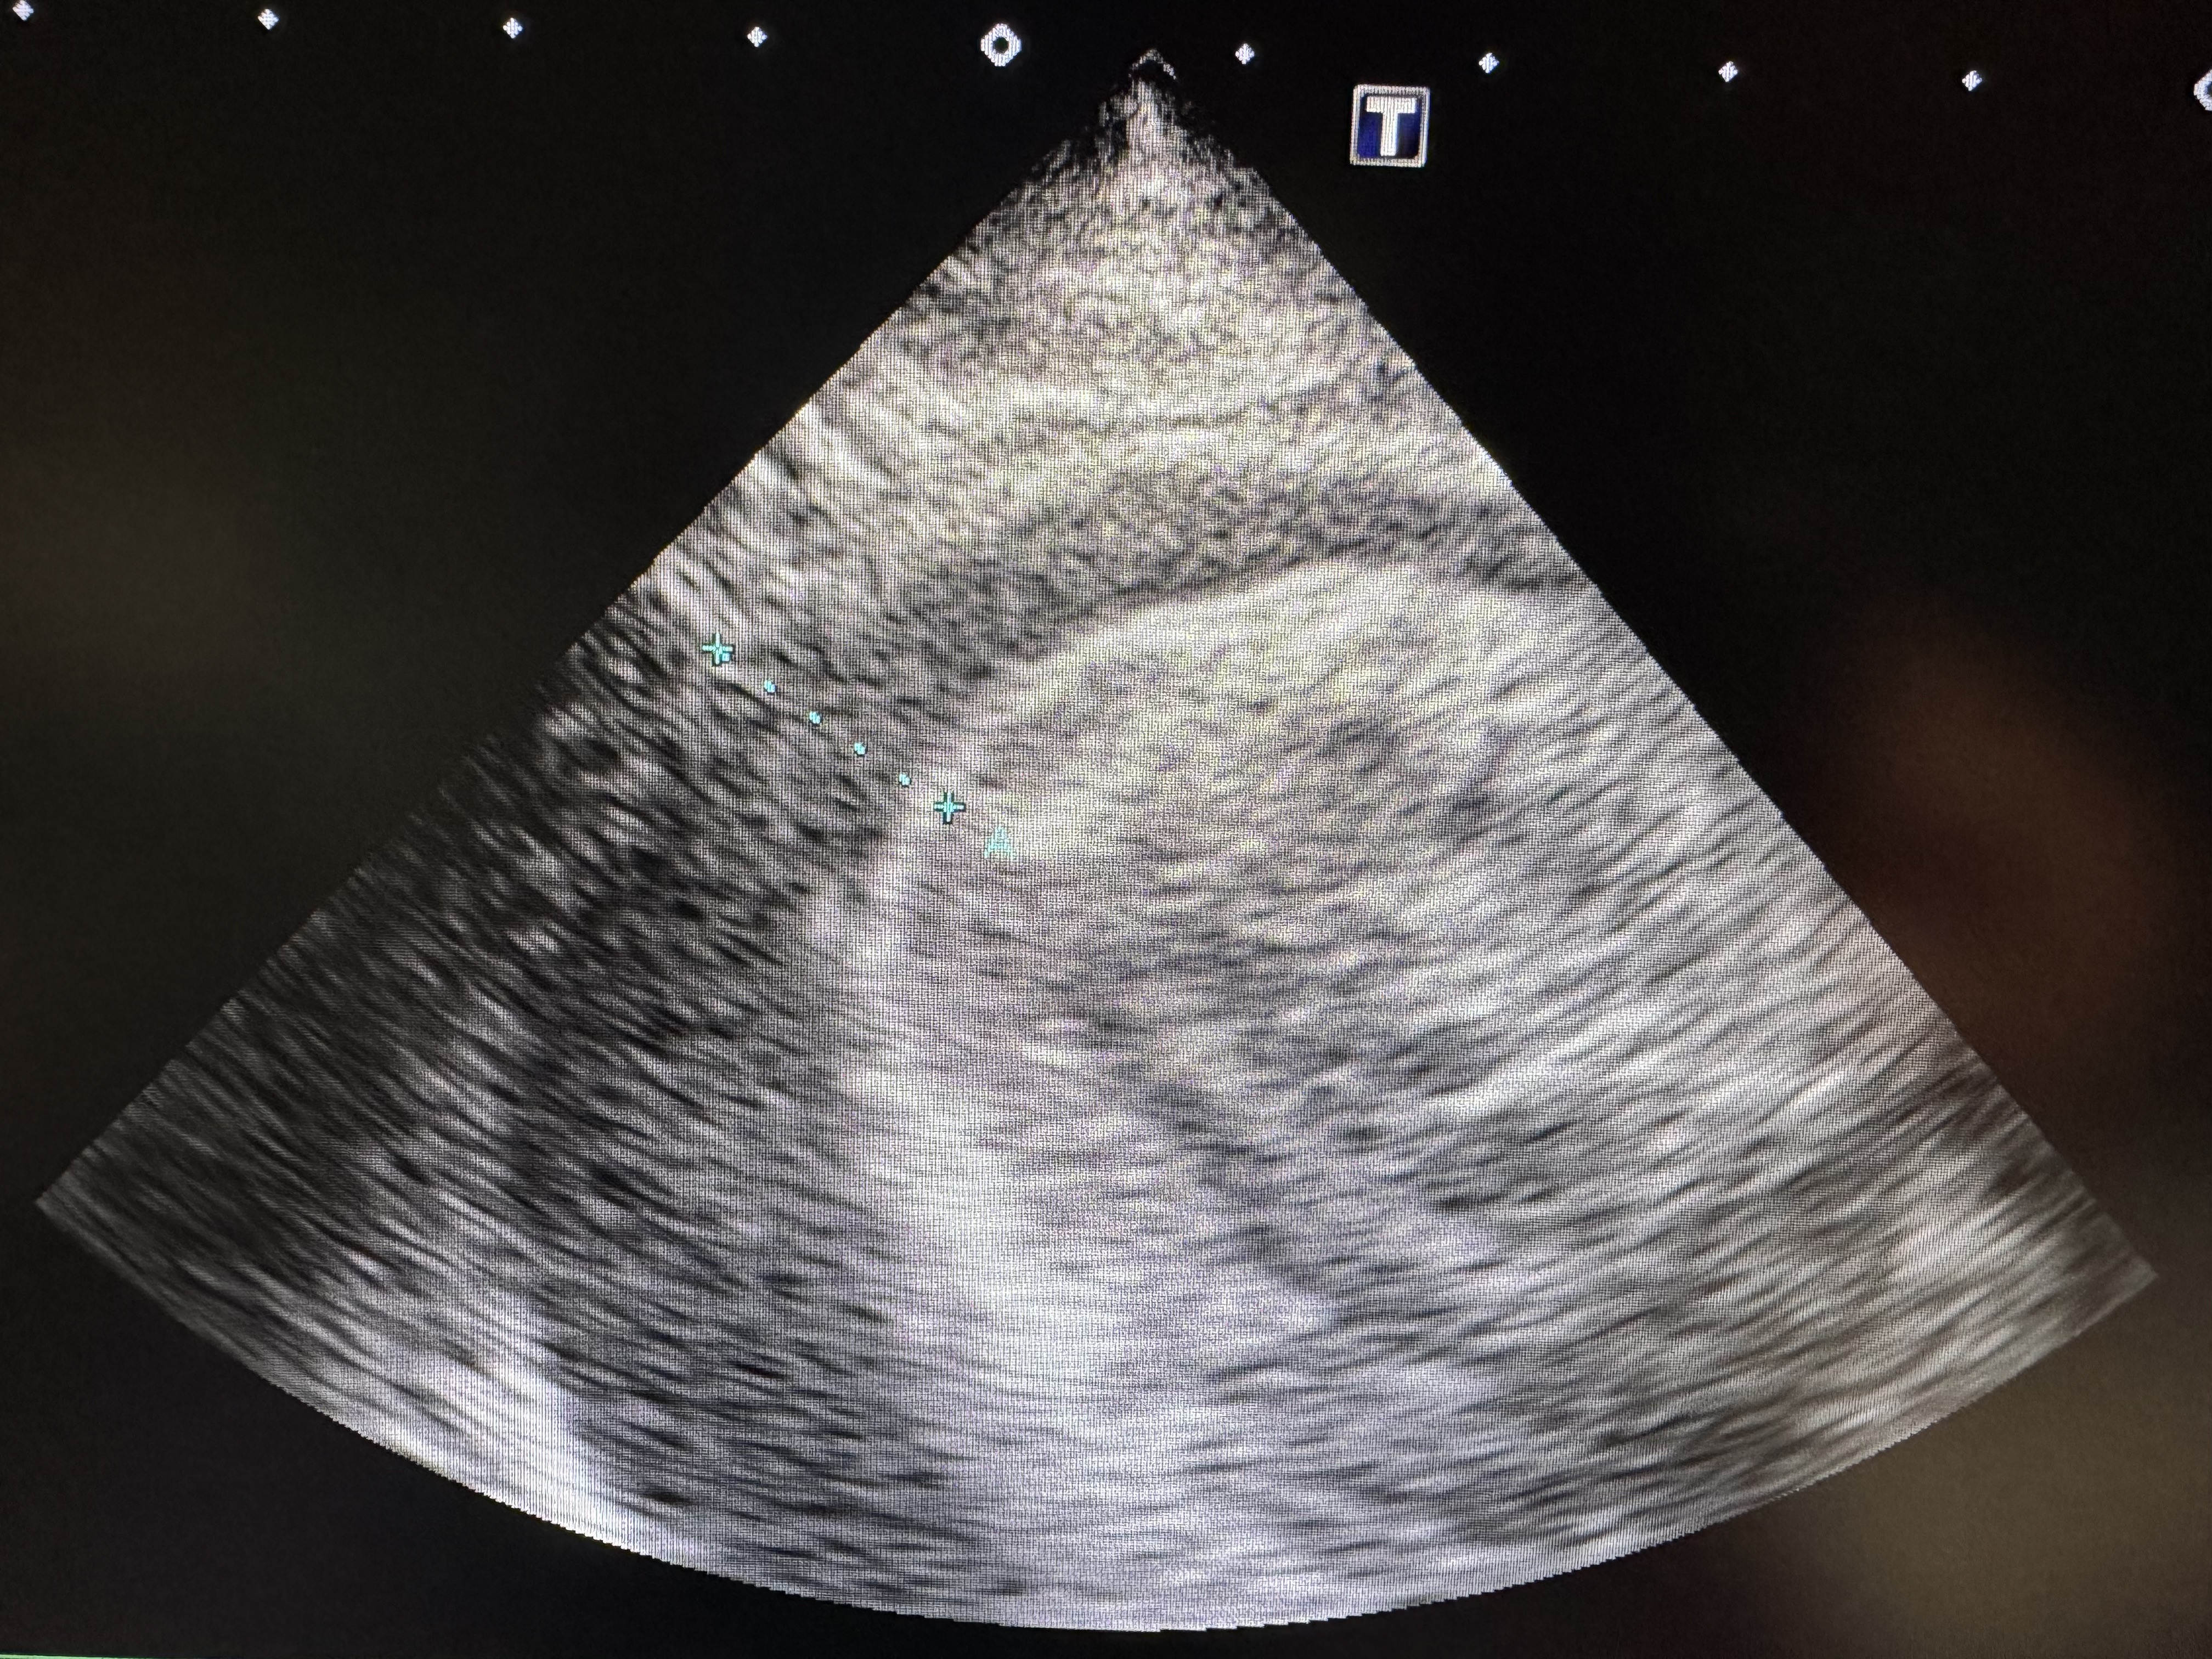

3. 超音波検査(エコー)

心嚢液の貯留を直接確認することができ、確定診断に役立ちます。

この心臓エコーの画像は、10歳のゴールデンレトリバーの子のものです。急に元気がなくなって立てなくなったということで来院されました。血液検査では異常がなく、レントゲンでも心肥大が認められるものの胸水の所見はありませんでした。しかしながら、股動脈圧が弱く、聴診で心臓の音が聞き取れない異常があり、循環異常の兆候が認められたため、心臓エコー検査を実施したところ心タンポナーゼであることが診断された症例です。心臓の周りに黒いスペース(液体貯留の初見)があり、心臓が十分に拡張できない状況にあるため、緊急に心嚢穿刺を行い、心嚢に溜まった心嚢水を摘出しました。

心タンポナーゼの時は写真のような血様の液体が排出されることが多いです。心臓にできた腫瘍からの出血や、原因が特定できない特発性のことがあります。心嚢水を抜いた後再度液体が貯留することがなければ、ある程度の寛解期間(健康な状態が続く期間)が得られることがあります。この子も翌々日くらいから元気が出てきており、現在は普通の生活をしています。